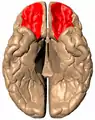

المكان التقريبي للقشرة الجبهية الحجاجية